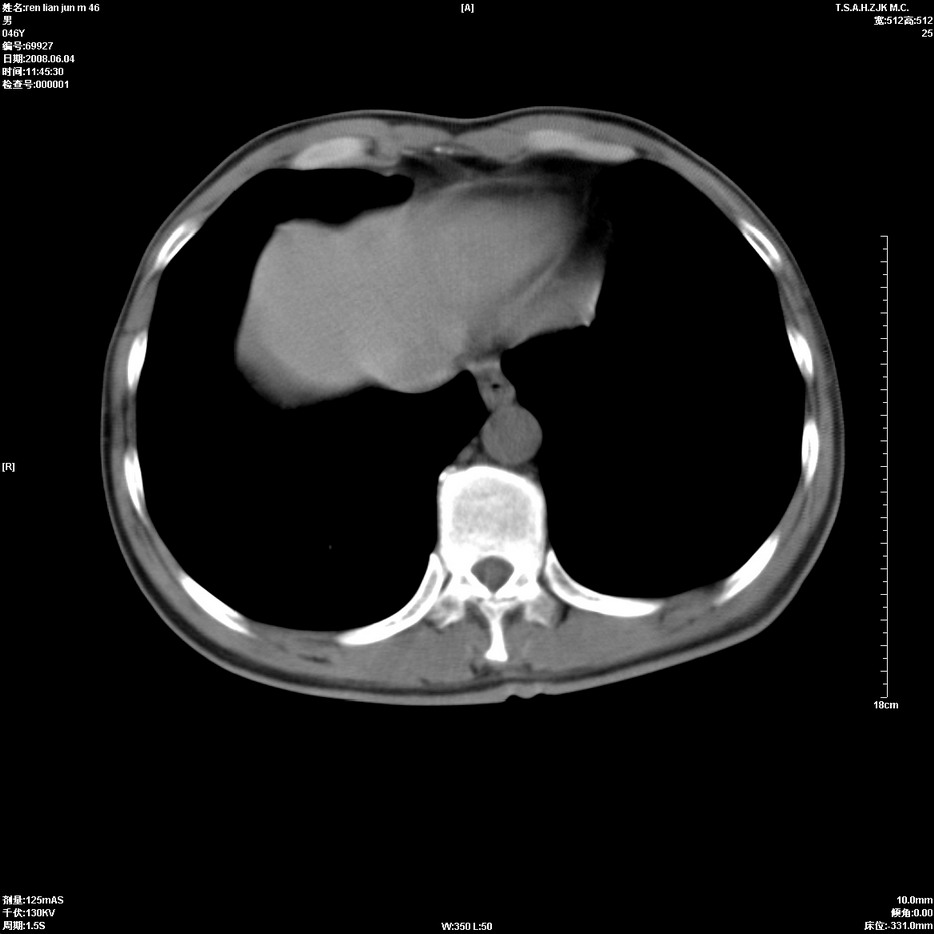

以下是引用qiu999在2008-6-5 17:14:00的发言:[br]考虑右肺中心型肺癌.颅内应做增强检查.

以下是引用形影不离在2008-6-5 19:18:00的发言:[br]右肺中心型肺癌并纵隔及左侧腋窝淋巴结转移,颅内应做增强检查。

以下是引用杀毒软件在2008-6-5 18:33:00的发言:[br]支持考虑右肺中心型肺癌,颅内病变是不是转移,不好说